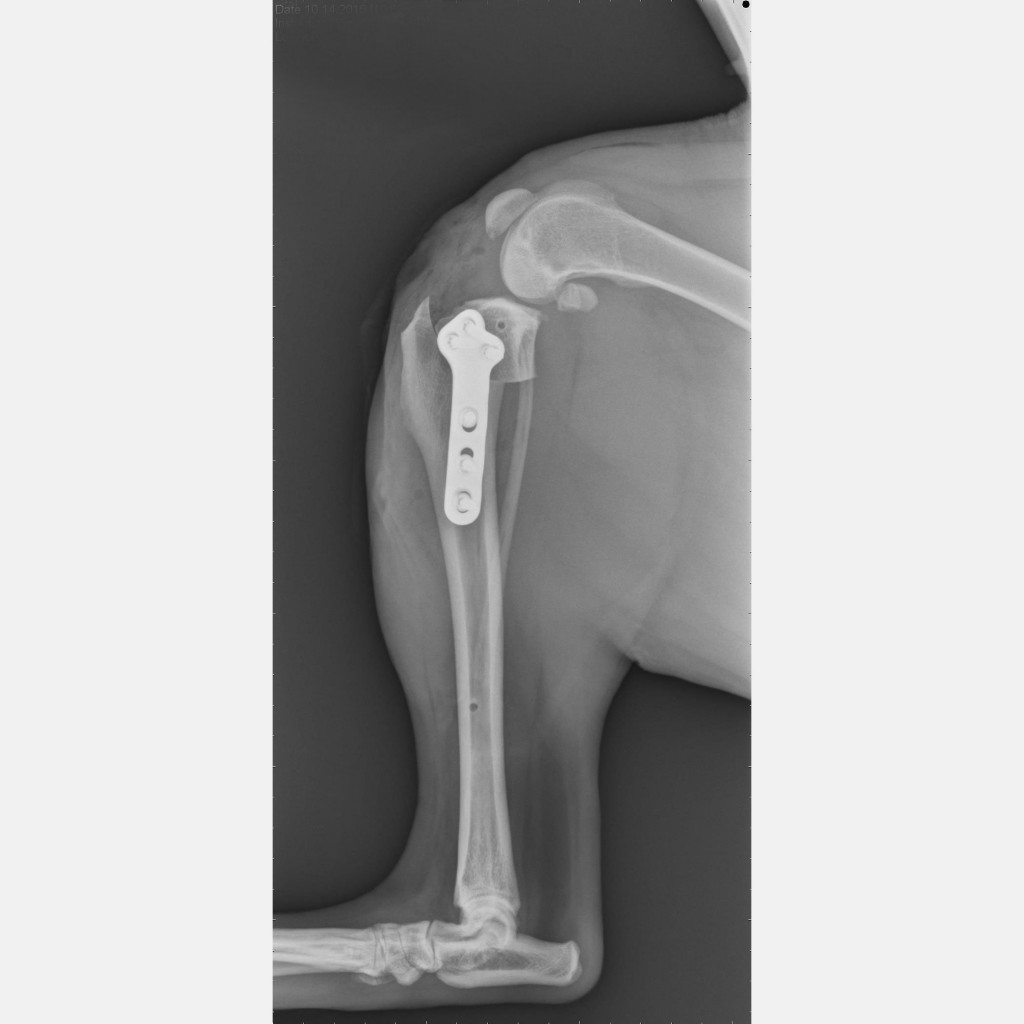

tplo Postoperative view of a TPLO procedure from the front Veterinary Surgical Specialists Tplo Surgery And Stairs That being said, sometimes they are unavoidable. In this comprehensive guide to dog tplo recovery, we have explored the different stages of healing that your furry friend will go. As a general rule, stairs are frowned upon early in the recovery period. In the beginning stages, right after surgery and until your veterinarian. Stairs, like jumping, will over stress the. Tplo Surgery And Stairs.